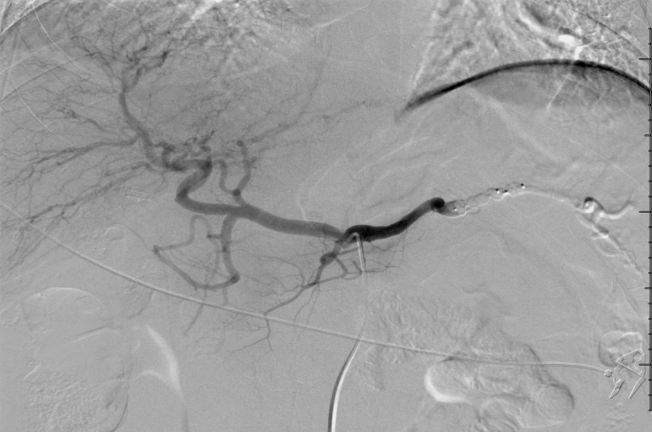

血管塞技术,技术进步血管塞(Plugs)释放已经不需要大直径的血管鞘。目前血管塞可以通过5F普通血管造影导管释放。血管塞的优点主要是经济和手术时间短。 与弹簧栓子的trapping 技术媲美

血管塞技术,技术进步血管塞(Plugs)释放已经不需要大直径的血管鞘。目前血管塞可以通过5F普通血管造影导管释放。血管塞的优点主要是经济和手术时间短。

与弹簧栓子的trapping 技术媲美